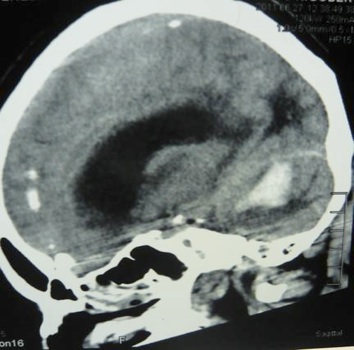

un homme de 56 ans, issu d’un milieu rural, hypertendu est admis le 22 juin 2011 au service de réanimation polyvalente. Avant son admission dans le service il présente un trouble de l’équilibre avec une pression artérielle de 250 /140 mmHg, puis s’installe rapidement un coma. Le patient a bénéficié d’un traitement par nicardipine intraveineux et du mannitol 10 %. Il a été ensuite transporté de façon non médicalisée vers la ville de Pointe noire pour conditionnement en vue de son transfert à Brazzaville. A l’arrivée à Pointe noire, le patient présente un coma profond et la saturation pulsée en oxygène est à 86 % ; il est bien coloré et l’état hémodynamique stable : fréquence cardiaque à 76 bpm et pression artérielle à 150/100 mmHg. Une intubation orotrachéale est réalisée après une induction à séquence rapide utilisant l’étomidate et la célocurine. La sédation associant midazolam et fentanyl est mise en route, ainsi qu’une ventilation mécanique. Le bilan biologique objective des leucocytes à 14700/ mm3, un taux d’hémoglobine de 16,6 g/dl, un taux d’hématocrite à 48,4 %, un nombre de plaquettes évalué à 319 000 ; une natrémie estimée à 136,9 mEq/l, une kaliémie de 5,0 mEq/l ; un taux de prothrombine de 84 %. L’électrocardiogramme montre une tachycardie régulière sinusale. La tomodensitométrie cérébrale révèle un hématome cérébelleux de 59 mm × 39 mm avec effet de masse sur le quatrième ventricule et une dilatation triventriculaire sus-jacente (figure 1). Au regard de ces aspects tomodensitométriques, un transfert vers le service de réanimation polyvalente du Centre Hospitalier Universitaire de Brazzaville est demandé pour une prise en charge optimale. A l’arrivée au service de réanimation polyvalente, la sédation était de niveau 6 selon le score de Ramsay [5], la température à 37° C, la SpO2 à 98 %, la fréquence cardiaque à 100/min et la tension artérielle de 160/90 mm Hg. La tomodensitométrie de contrôle mettait en évidence un hématome du cervelet avec une hydrocéphalie importante (figure 2). Aprèsavis du neurochirurgien, une dérivation externe du liquide céphalo-rachidien (LCR) a été réalisée, produisant quotidiennement en moyenne 400 ml de LCR. Une amélioration de l’état neurologique a été notée au deuxième jour, le score de Glasgow était évalué à 8/10, le patient étant toujours intubé. Le patient était décédé à j12 d’hospitalisation, des suites d’une pneumopathie hypoxémiante nosocomiale tardive, diagnostiquée à j8.